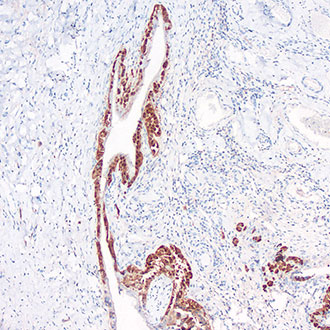

IHC

免疫组织化学(IHC)